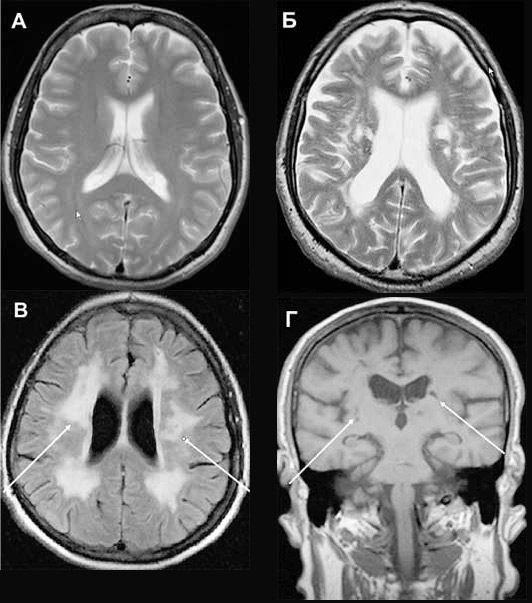

Мультиинфарктная деменция при КТ головного мозга.

Когнитивные нарушения , развившиеся в результате нескольких инсультов , называют мультиинфарктной деменцией.

КТ или МРТ выявляют множественные инфаркты головного мозга.